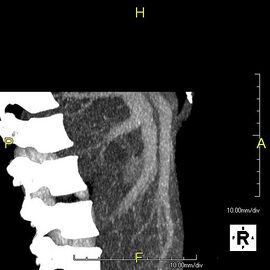

صورة مقطعية محورية تظهر أوردة كبدية شاذة تنتشر على السطح الأمامي تحت المحفظة للكبد.[73]